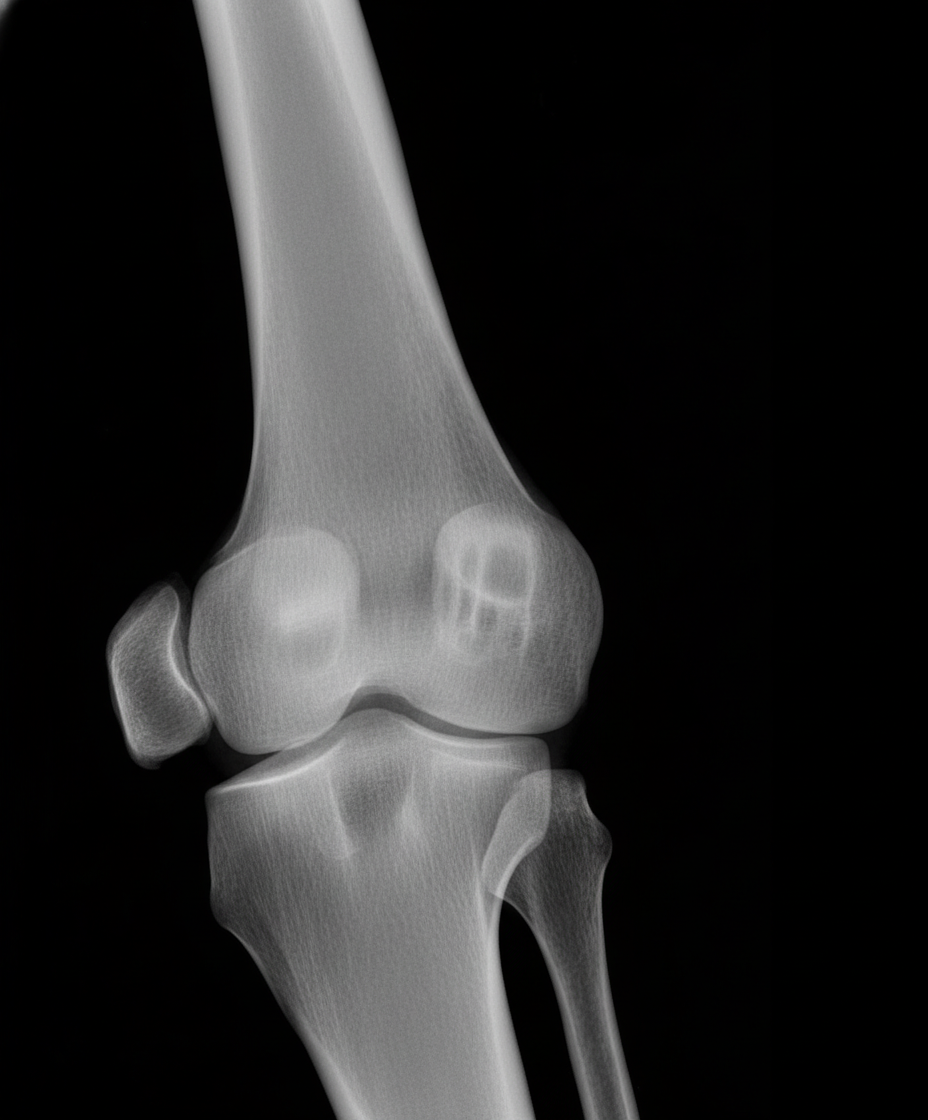

- X-ray Findings: The initial imaging modality.

- Location: Most commonly affects the diaphysis of long bones (femur, tibia, humerus) and the pelvis.

- Appearance: Poorly-defined, lytic lesion with a permeative or "moth-eaten" pattern of bone destruction.

- Periosteal Reaction: Key diagnostic signs.

- "Onion skin" appearance: A lamellated, layered reaction.

- Codman triangle: A triangular area of new subperiosteal bone.

- A "sunburst" or "hair-on-end" pattern can also occur.

⭐ Exam Favourite: The classic description is a destructive lesion in the diaphysis of a long bone with an "onion skin" periosteal reaction.